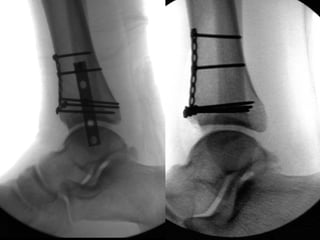

Before Fixation After Fixation

43°

42°

Syndesmosis:

Obtaining a Reduction

DF unnecessary Tornetta JBJS 2001

Incidence of malreduction based on CT scan

“standard”: >50%

– Gardner et al. FAI 27: 788-92, 2006.

Ways to ensure appropriate reduction:

– Direct visualization

• FAI 30: 419-26, 2009

– Radiographic imaging in multiple planes

• Injury 35: 814-18, 2004.

Problem?

The CT definition of an anatomic

syndesmosis

Elgafy et al. Skeletal Radiology 39: 559-64, 2010